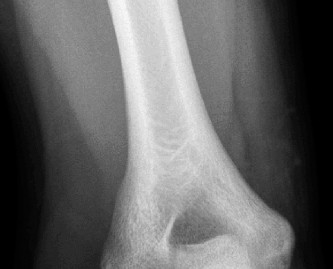

CASE 40 A 16-year-old male baseball player presents to your office for evaluati…

CASE 21 A 15-year-old high school football linebacker is seen in your office fo…

CASE 11 A patient presents to your clinic with ulnar-sided wrist pain. X-ray is…

CASE 21 Following an intense game of football, a player is brought to you with …

CASE 11 A 45-year-old man is brought to the trauma bay after falling from his r…